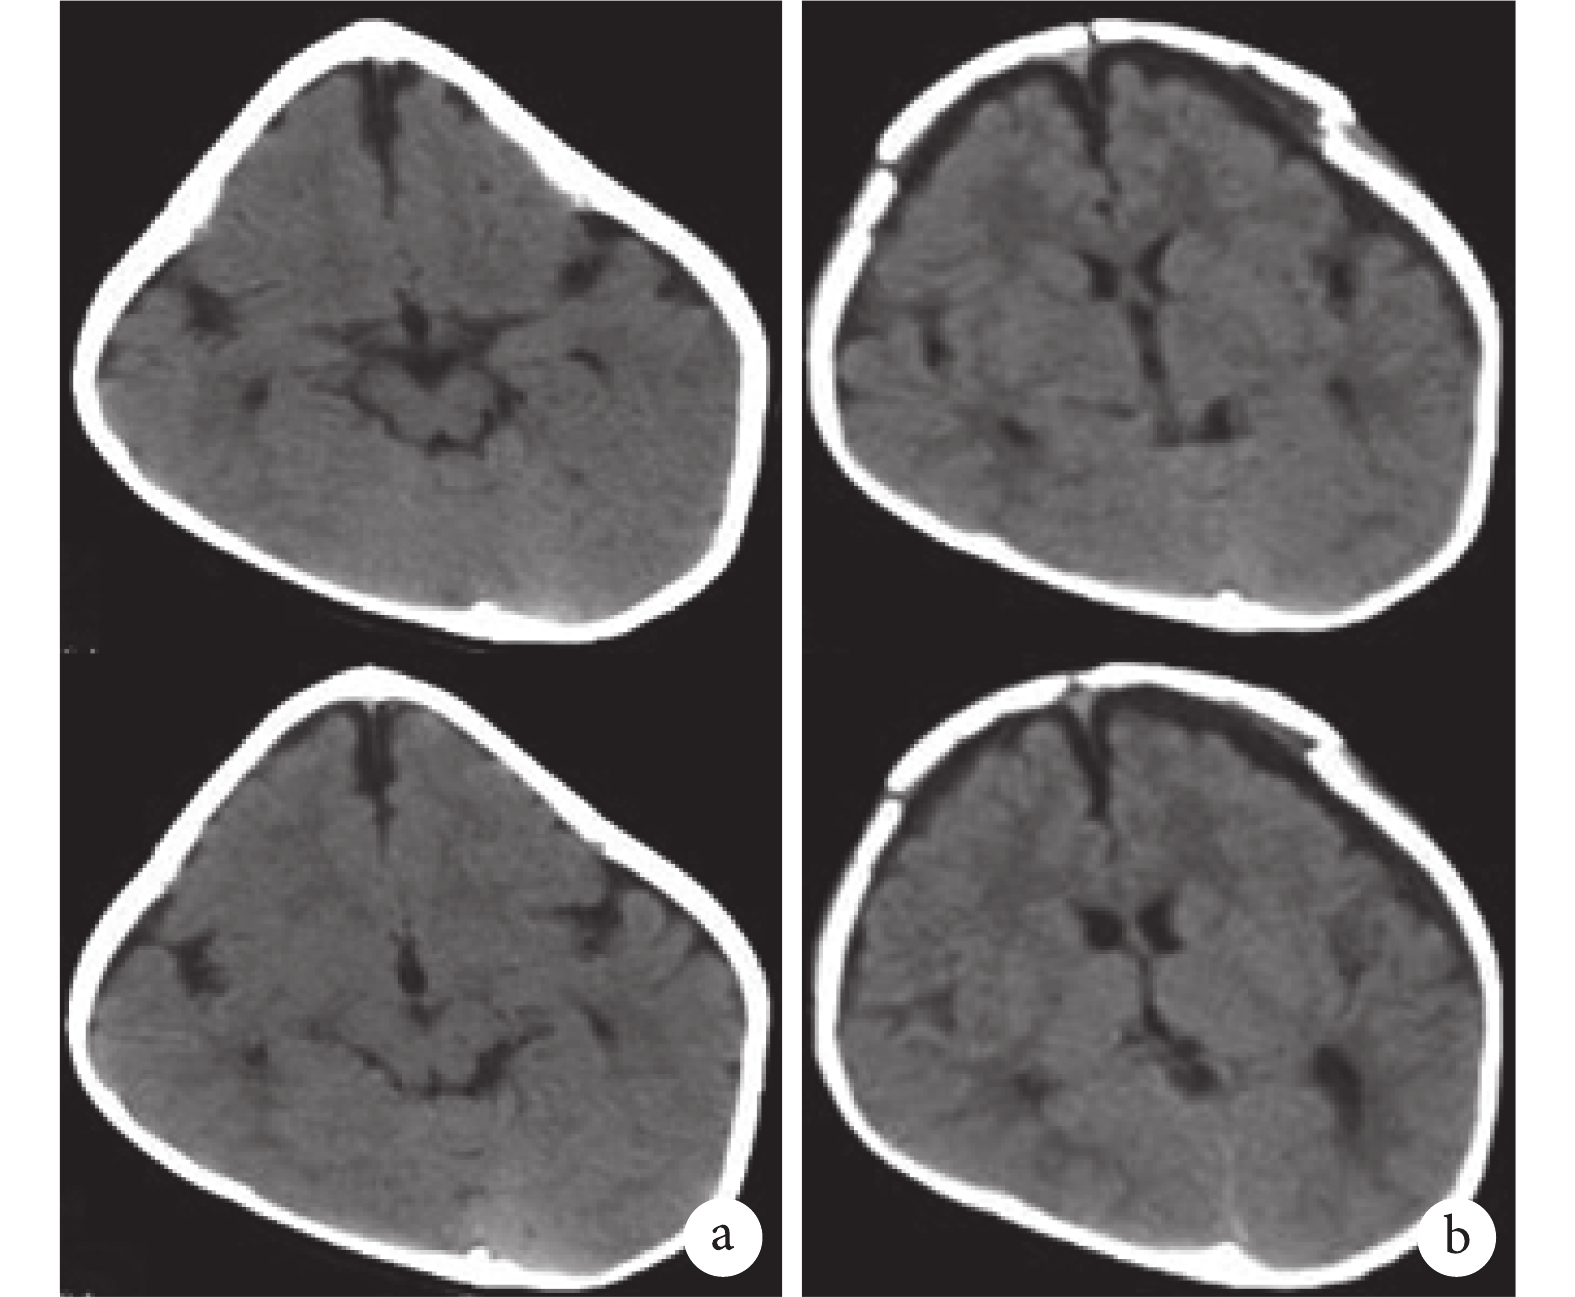

患兒在術后獲得了理想的頭型。通過 CT 檢查驗證,手術結果與模擬術后頭顱模型一致,術后患兒顱骨 CT 圖像見圖 8。

患兒經過激素沖擊治療后,病情好轉,運用 3D 打印技術行外科手術整形治療,首先運用斷層掃描(CT)技術獲得頭顱圖像,接著通過使用圖像處理軟件 Mimics18.0 和 3-matic10.0 進行三維圖像建模和術前的手術模擬,重建的顱骨模型保存為 STL 格式,并通過數字接口輸入 3D 打印機。手術計劃采用顱蓋重建術式,一是將患兒畸形的顱骨全部拆卸,松解被壓迫的大腦;二是對顱骨進行分割,逐個塑成需要的形狀,再重新拼接(圖 5、6、7)。